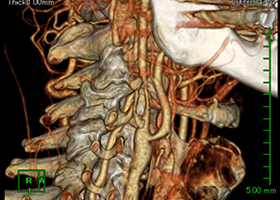

造影三次元CT画像

左前頭側頭開頭で動脈瘤クリッピング術を行った。手術中は脳血管撮影装置を用いたHybrid手術を施行し、動脈瘤の消失を手術中に確認する。

造影3DCT検査:錐体斜台部巨大髄膜腫認め

神経や血管を巻き込んでいます。 -